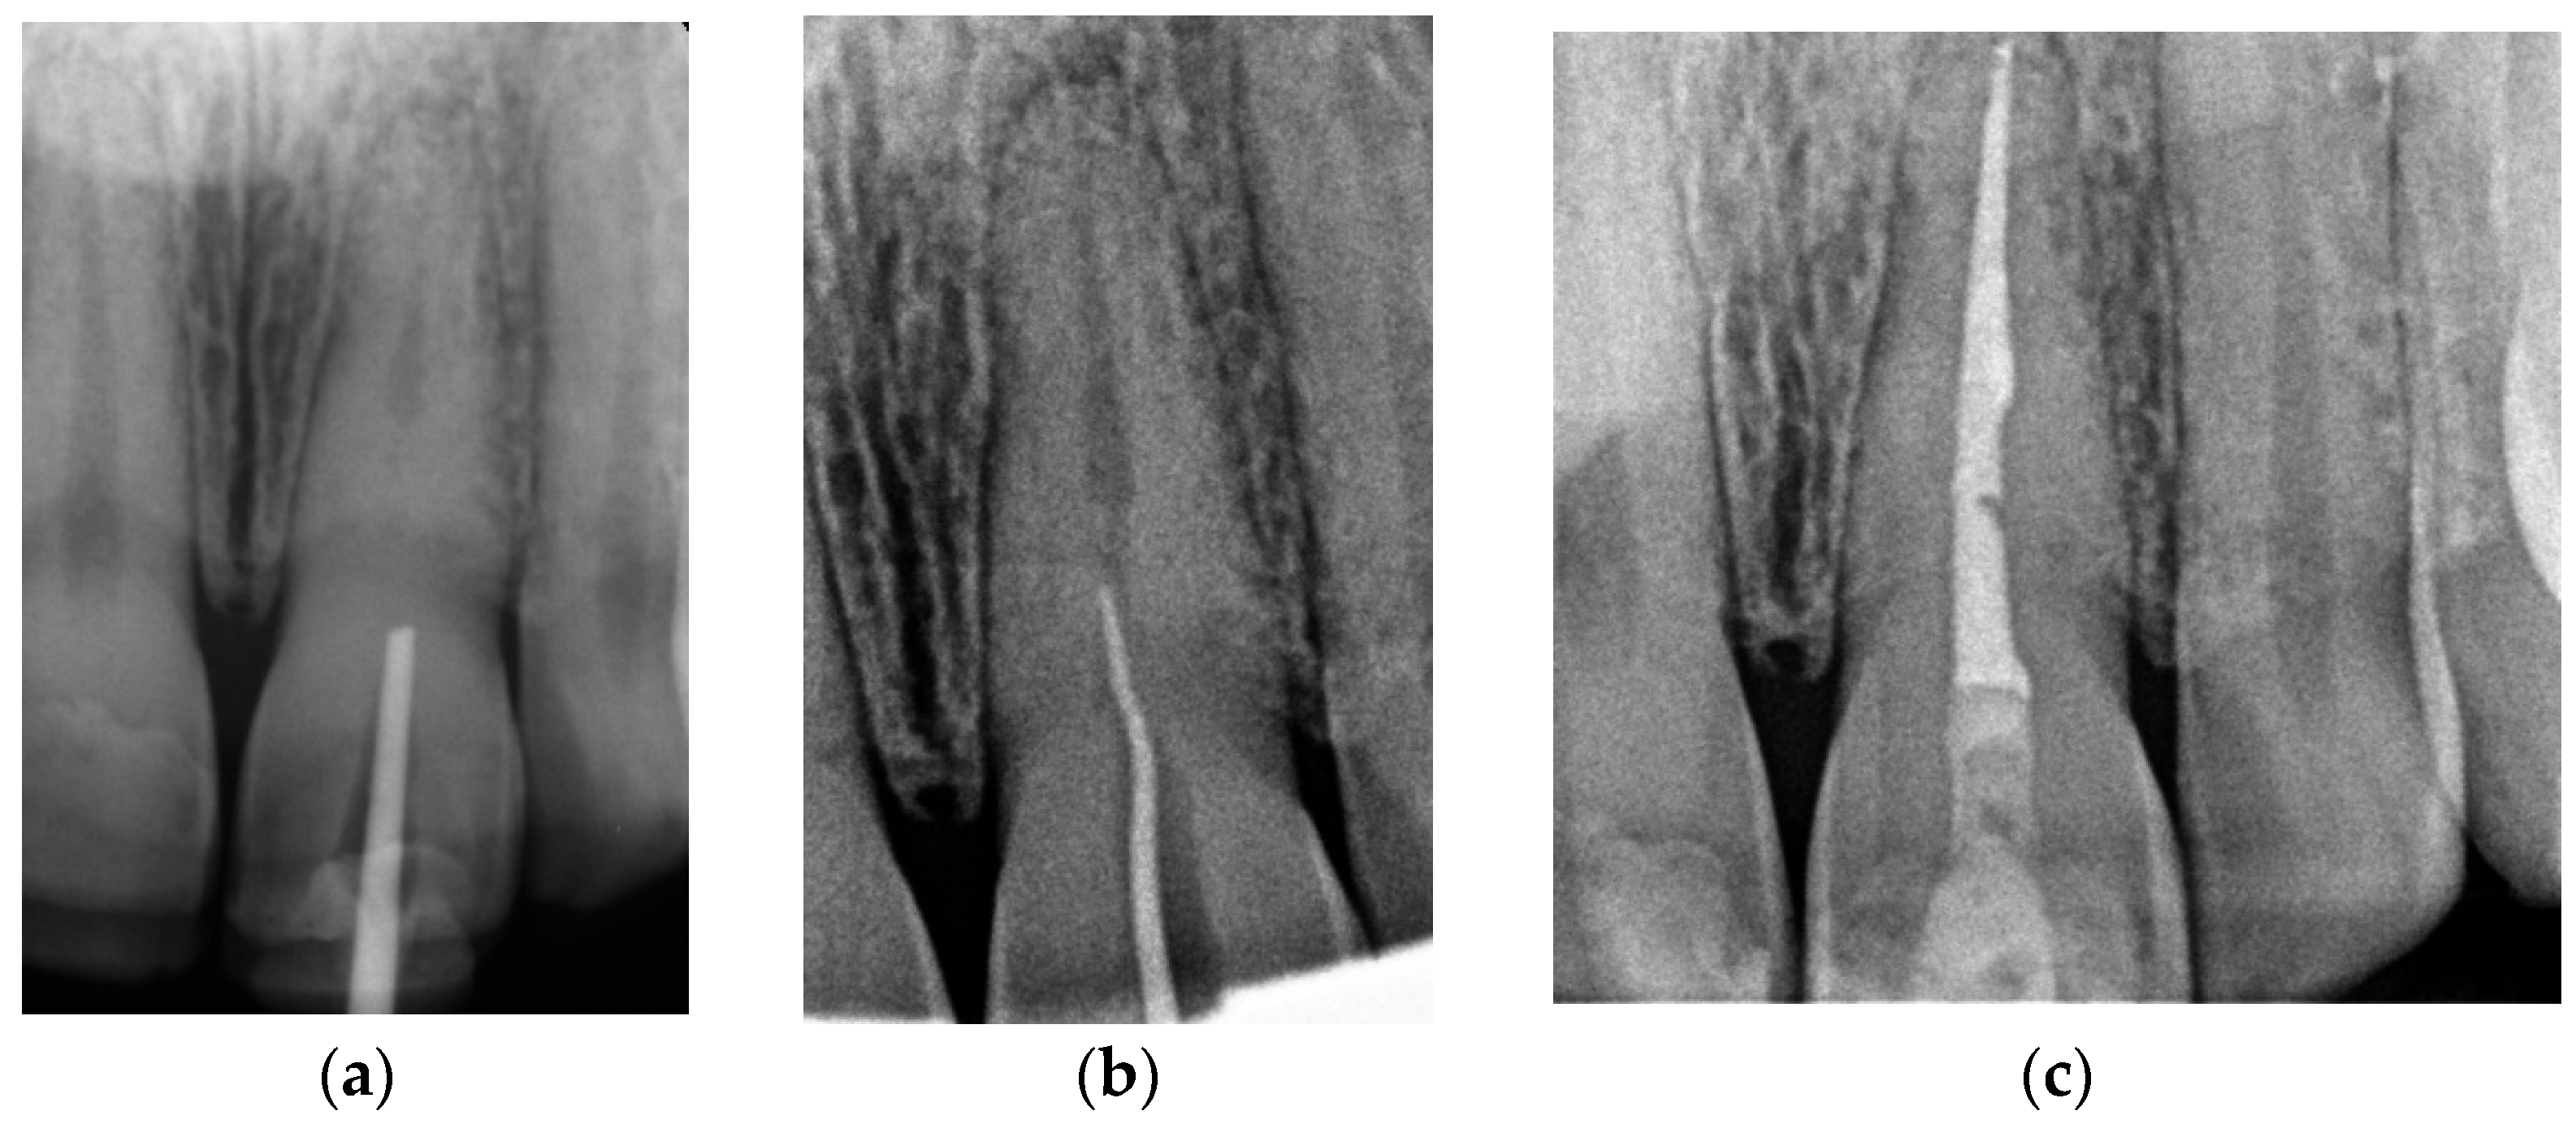

Canal Treatment

The correct fit of the guide was verified before and after the rubber dam was placed. For local anaesthesia, 1.7 mL Ubistesin forte (3 M ESPE, Seefeld, Germany) was administered (articaini hydrochloridum 40 mg + epinephrine hydrochloridum 0.012/1 mL). A small sign was made on the enamel surface through the guide to indicate the access point. The enamel was removed in a minimally invasive manner with a diamond bur until the dentine was exposed. The guide was placed on the teeth and the treatment was performed with Munce Discovery Bur #1 (CJM Engineering, Santa Barbara, CA, USA) with a speed of 10,000 rpm. This bur was a round carbide bur with a head diameter of 0.8 mm (ISO head size 08) and a total length of between 31 and 34 mm. The guide was removed every 2 mm to rinse the cavity, control endodontic access using an optical microscope, and clean the bur. After the bur reached the estimated depth, the C-Pilot #10 and #15 files (VDW, Munich, Germany) were used to check the canal position. Radiographic examination was performed to confirm correct canal access (Figure 15). The canal was reached at a length of 22 mm from the top of the guide sleeve - 1 mm deeper than the virtually planned depth. Once the remaining canal was reached, the length was confirmed with an electronic apex locator (Raypex 6; VDW, Munich, Germany). A conventional root canal treatment followed. The canal was irrigated with 5.25% sodium hypochlorite (NaOCl), including passive ultrasonic activation, and instrumented with ProTaper Gold (Dentsply Sirona Endodontics, Ballaigues, Switzerland) up to the F3 file size (0.30/0.09v). It was dried with paper points and obturated with vertically condensed gutta-percha and epoxy sealer (AH Plus, De Trey, Konstanz, Germany). The access cavity was cleaned and filled with a composite resin (Estelite Asteria, Tokuyama Dental Corporation, Tokyo, Japan).

Figure 15. Radiographic examination was used to confirm (a) correct path of access pathway during procedure and (b) correct root canal access; (c) post-obturation radiograph.